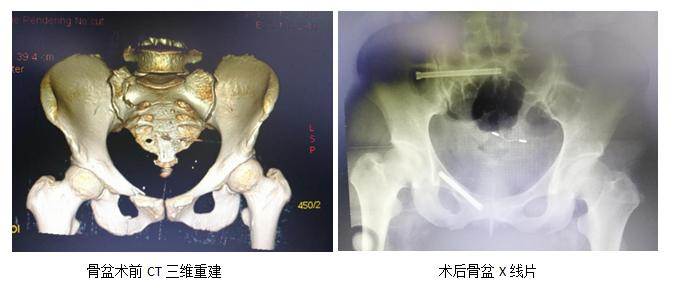

经骨与创伤中心专家团队激烈讨论,结合患者基本情况,蒋电明主任毅然决然的做出一个决定——患者全身多处骨折均采取微创闭合复位!诚然,微创闭合复位是目前患者最好的选择方式——创伤小,出血少,手术打击大幅减轻,术后恢复快等,但对术者的要求也相当苛刻,在不能直视和直接触摸骨折方位的情况下,仅根据主刀的手感和临床经验将骨折复位,再将固定物以最完美的角度打入骨折处并将其妥善固定,唯一的“眼睛”就是不断的透视射线,郑明副主任医师勇挑重任。

随着麻醉的起效,患者全身多处骨折闭合复位内固定手术顺利进展,凭着扎实的临床经验,主刀医生郑明顺利置入骨盆后侧的骶髂螺钉及前侧的耻骨支通道螺钉。在助手牵拉、旋转、复位的密切配合下,精准的将患者的多段腓骨粉碎性骨折闭合复位成功!接下来的胫骨髓内钉闭合复位内固定也成功开展。